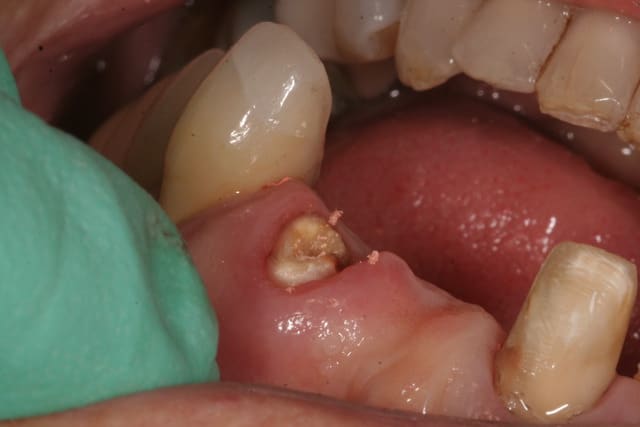

femme, 62 ans, santé RAS, qui arrive avec un bridge (fait par le confrère que j'ai remplacé il y a 2 ans) 11-(21)-22 mobile. 22 fracturée, je dépose, fais un provisoire.

Ce qui est sûr, c'est que je n'irai pas mettre un bridge sur cette latérale. Et même une couronne unitaire, j'hésiterais: trop grêle. Pas de ferule effect, racine trop courte. Bref tout pour plaire.